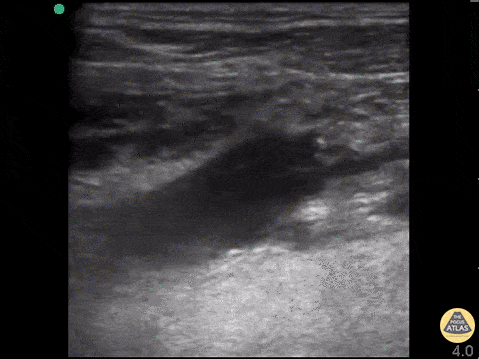

Vascular - Lemierre Syndrome

25yo w/ no PMH had left molar extracted 10days prior, presents with four days of subjective fever, malaise, and increasing pain to L neck, tachypneic and hypoxic and was intubated w/ central line placed. POCUS scans through the jugular vein to reveal a clot. CT angiogram showed left internal jugular vein thrombosis, low attenuation L temporal lobe concerning for parenchymal abscess. Dr. John F. Kilpatrick - Kings County/SUNY Downstate Emergency Medicine